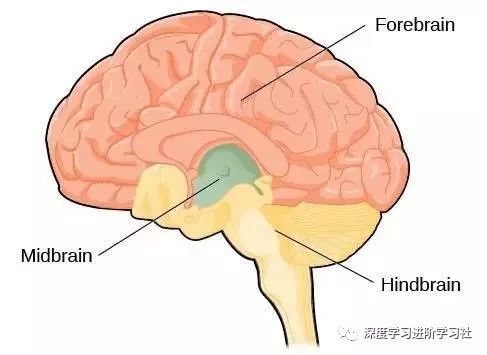

让我们使用半球横截面看看大脑的主要部分。因此,这是你脑袋里大脑的样子:

现在,让我们把大脑取出来,并删除左半球,这让我们能看清楚内部。

神经学家 Paul MacLean 做了一个简单的示意图,说明我们前面谈到的爬行动物大脑在进化中的第一次出现,然后是在哺乳动物兴盛阶段形成的古生哺乳动物脑和新哺乳动物脑。

也可以这么表示

让我们来看看每个部分:

脑干及小脑(The Brain Stem and Cerebellum)

这是我们的大脑最古老的部分:

中脑(The midbrain)

中脑与视觉,听觉,动作控制,警觉性,体温控制有关,还有一堆其他的事情。大脑被分为了前脑、中脑和后脑。